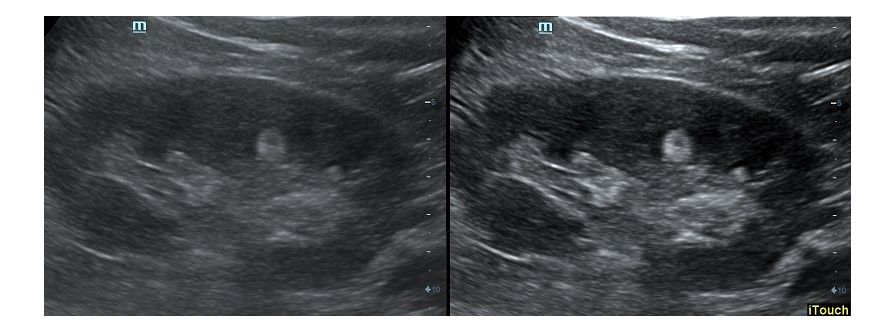

Оптимизация изображения происходит и за счет постобработки. Наиболее часто используемый инструмент - общее усиление (Gain). Усиление делает изображение «ярче», но чем сильнее усиление, тем меньше различия между структурами. Также используются усиление по времени (TGC) и усиление по длине (LGC), которые позволяют изменять отображение на экране послойно, позволяя подсветить гипоэхогенные участки, или, наоборот, снизить визуально эхогенность слишком ярких моментов. Данный вид оптимизации требует много времени, для упрощения работы доктора на приборах Mindray внедрена система автоматической оптимизации - iTouch.